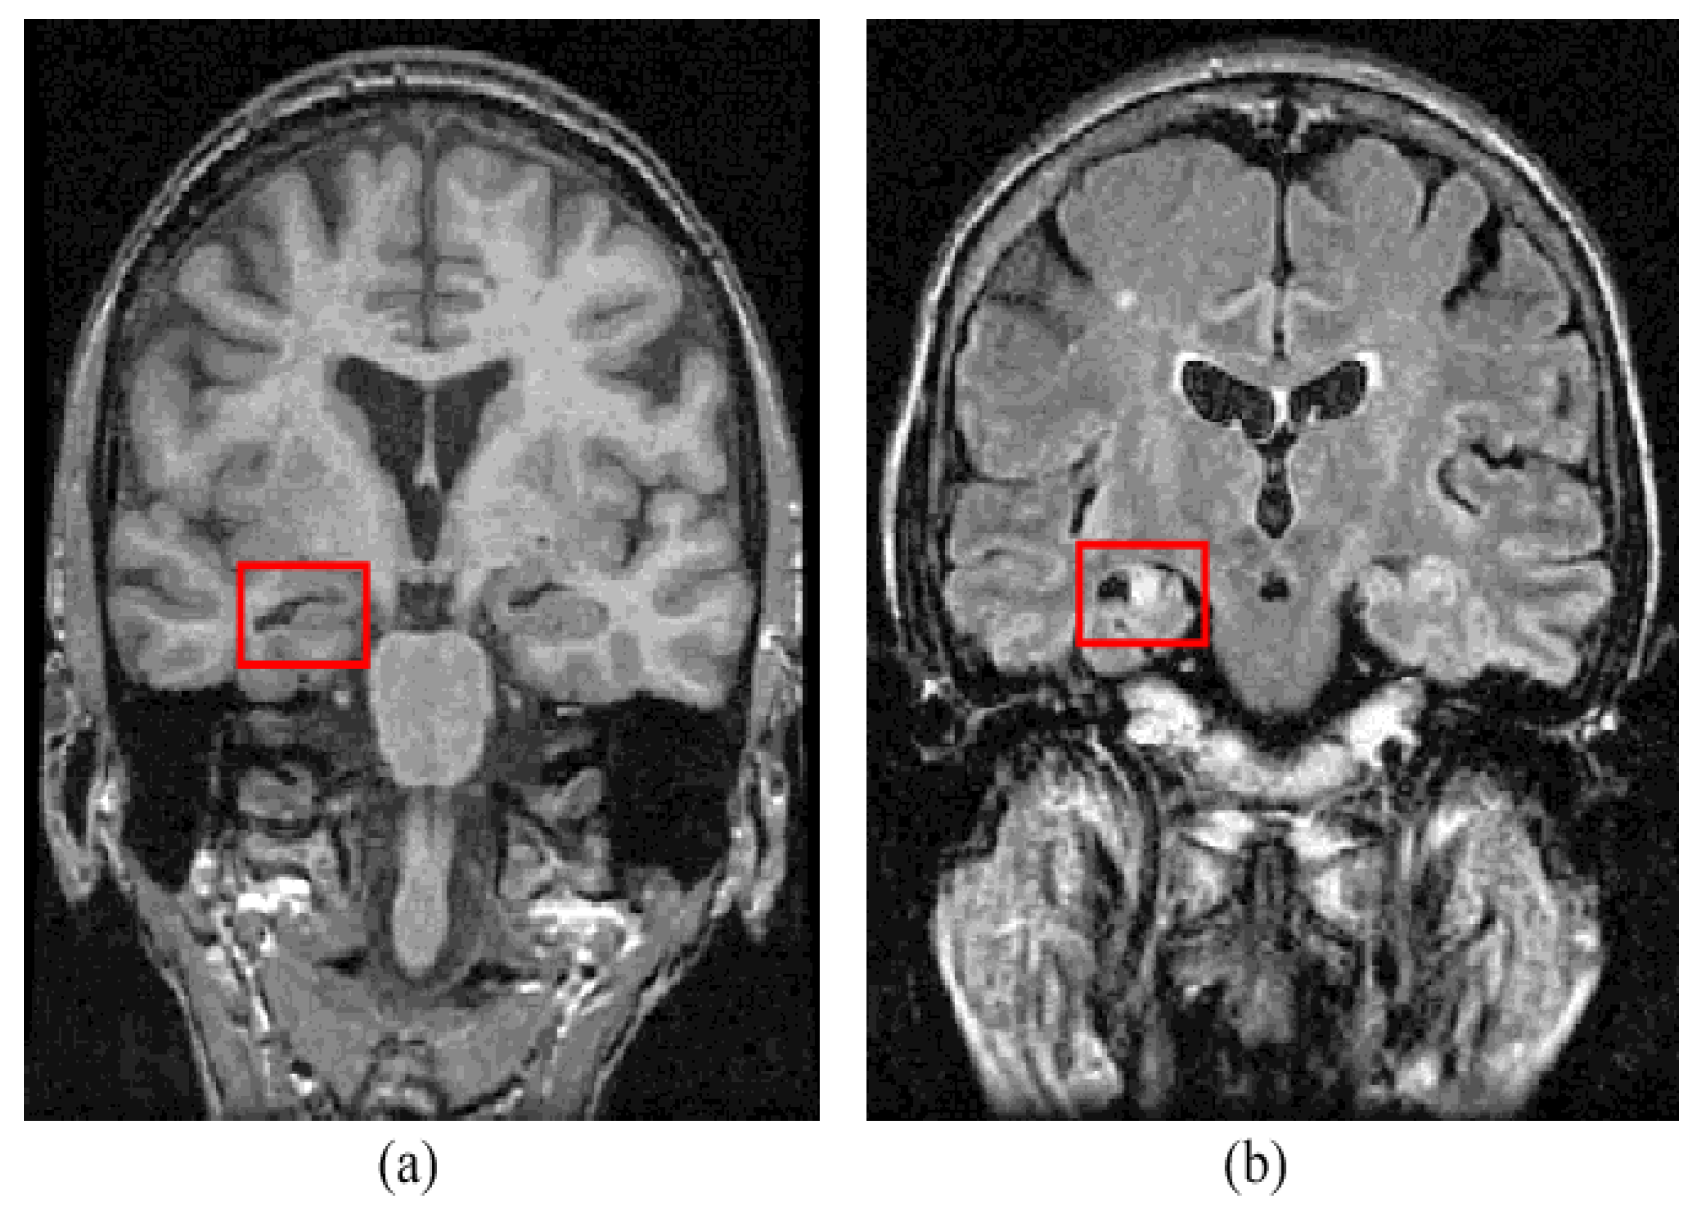

Figure 2.

Mesial temporal sclerosis lesion (a) T1-weighted MRI and (b) FLAIR MRI [11].